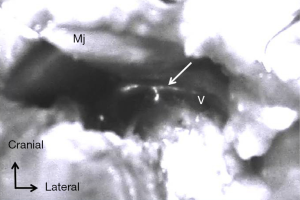

Patients with clinically node-positive axilla initially received an intra-dermal injection of 0.5–1.0 mL (5 mg/mL) indocyanine green as a tracing agent (ICG; Diagnogreen; Daiichi Sankyo, Co., Ltd., Tokyo, Japan) at the upper and inner ipsilateral arm using a 1-mL syringe with a 26-gauge needle under general anesthesia before preparation for breast surgery. After massaging for approximately 5 min, the fluorescence signal was detected using an invisible near-infrared fluorescence imaging system (PDETM; Photo Dynamic Eye; Hamamatsu Photonics Company, Hamamatsu, Japan.) as flowing to the axilla from the upper extremity. Patients who had positive sentinel nodes as shown on SLNB received an ICG injection before ALND in a manner similar to that for patients with clinically node-positive axilla. After performing lumpectomy or mastectomy for breast cancer, we started to explore ARM nodes in the axillary field. ARM nodes and lymphatic ducts were identified as fluorescent objects in the axilla even if they did not exhibit a green-colored stain. The locations of all identified ARM nodes were marked on the map according to the surgical landmarks of the axilla as our previously reported. The limits of ALND were defined by the axillary vein, superiorly; the anterior serratus muscle, medially; and the anterior edge of the latissimus dorsi muscle, laterally. When fluorescent ARM nodes were located in the ALND field, they were separately removed to evaluate the pathological findings. On the other hand, when identified ARM nodes were outside the ALND field, they were spared. When we would start to dissect the just below the axillary vein, we evaluated the existence of CC not to disrupt the CC running around the vein during lymph node dissection.

Under fluorescence imaging using a PDETM System, we identified ARM lymph nodes and CC in 185 (89%) patients and 81 (39%) patients, respectively (Figure 1). All identified CC could be preserved, whereas the identified ARM nodes could be spared in 12 of 185 patients because these nodes were mostly located in ALND field at the axilla. Metastatic ARM nodes were identified in 68 of 177 (38.4%) patients with ARM nodes removed from the ALND field.